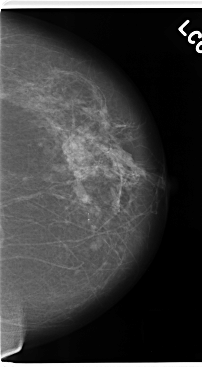

C_0172_1.LEFT_MLO

LEFT_MLO LINES 4720 PIXELS_PER_LINE 2816 BITS_PER_PIXEL 12 RESOLUTION 50 NON_OVERLAY